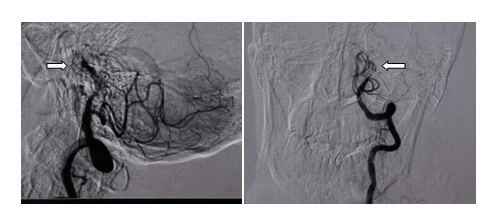

全脑血管造影提示患者颅内非常重要的一根大血管基底动脉闭塞,情况极及危重,患者随时有生命危险或遗留严重的后遗症如植物状态或偏瘫等,取栓是目前对患者最好的救治手段,跟家属沟通后,立即予以取栓治疗。

白箭头所指为闭塞的基底动脉